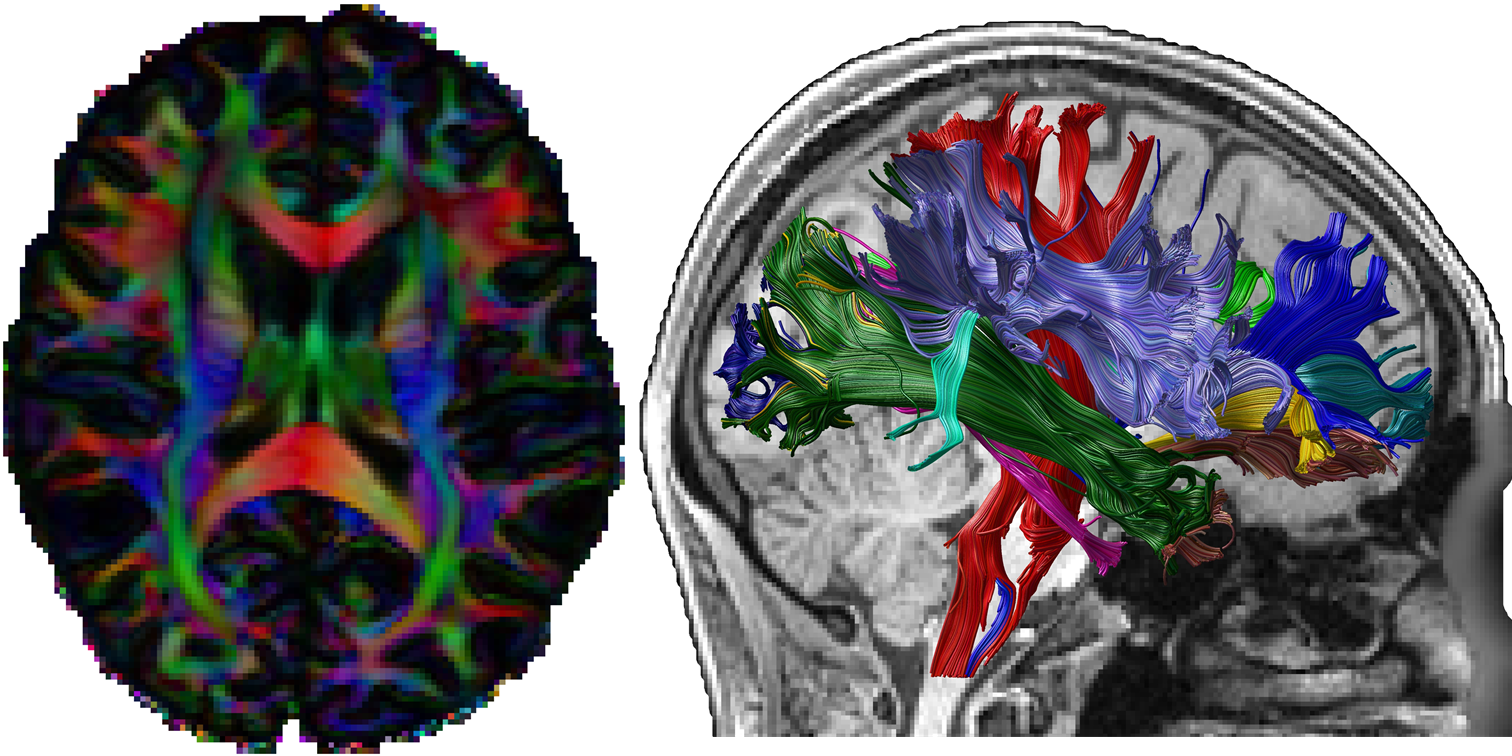

DeepDTI: High-fidelity Six-direction Diffusion Tensor Imaging using Deep Learning [PDF] [Video1] [Video2] [Tutorial] [Codes]

• Tian Q, Bilgic B, Fan Q, Ngamsombat C, Liao C, Hu Y, Witzel T, Setsompop K, Polimeni JR, Huang SY

• NeuroImage, 2020; 219: 117017

Diffusion MRI Tractography for Improved Transcranial MRI-guided Focused Ultrasound Thalamotomy Targeting for Essential Tremor [PDF] [Video] [Codes]

• Tian Q, Wintermark M, Elias WJ, Ghanouni P, Halpern CH, Henderson JM, Huss DS, Goubran M, Thaler C, Airan R, Zeineh M, Pauly KB, McNab JA

• NeuroImage: Clinical, 2018; 19:572-580